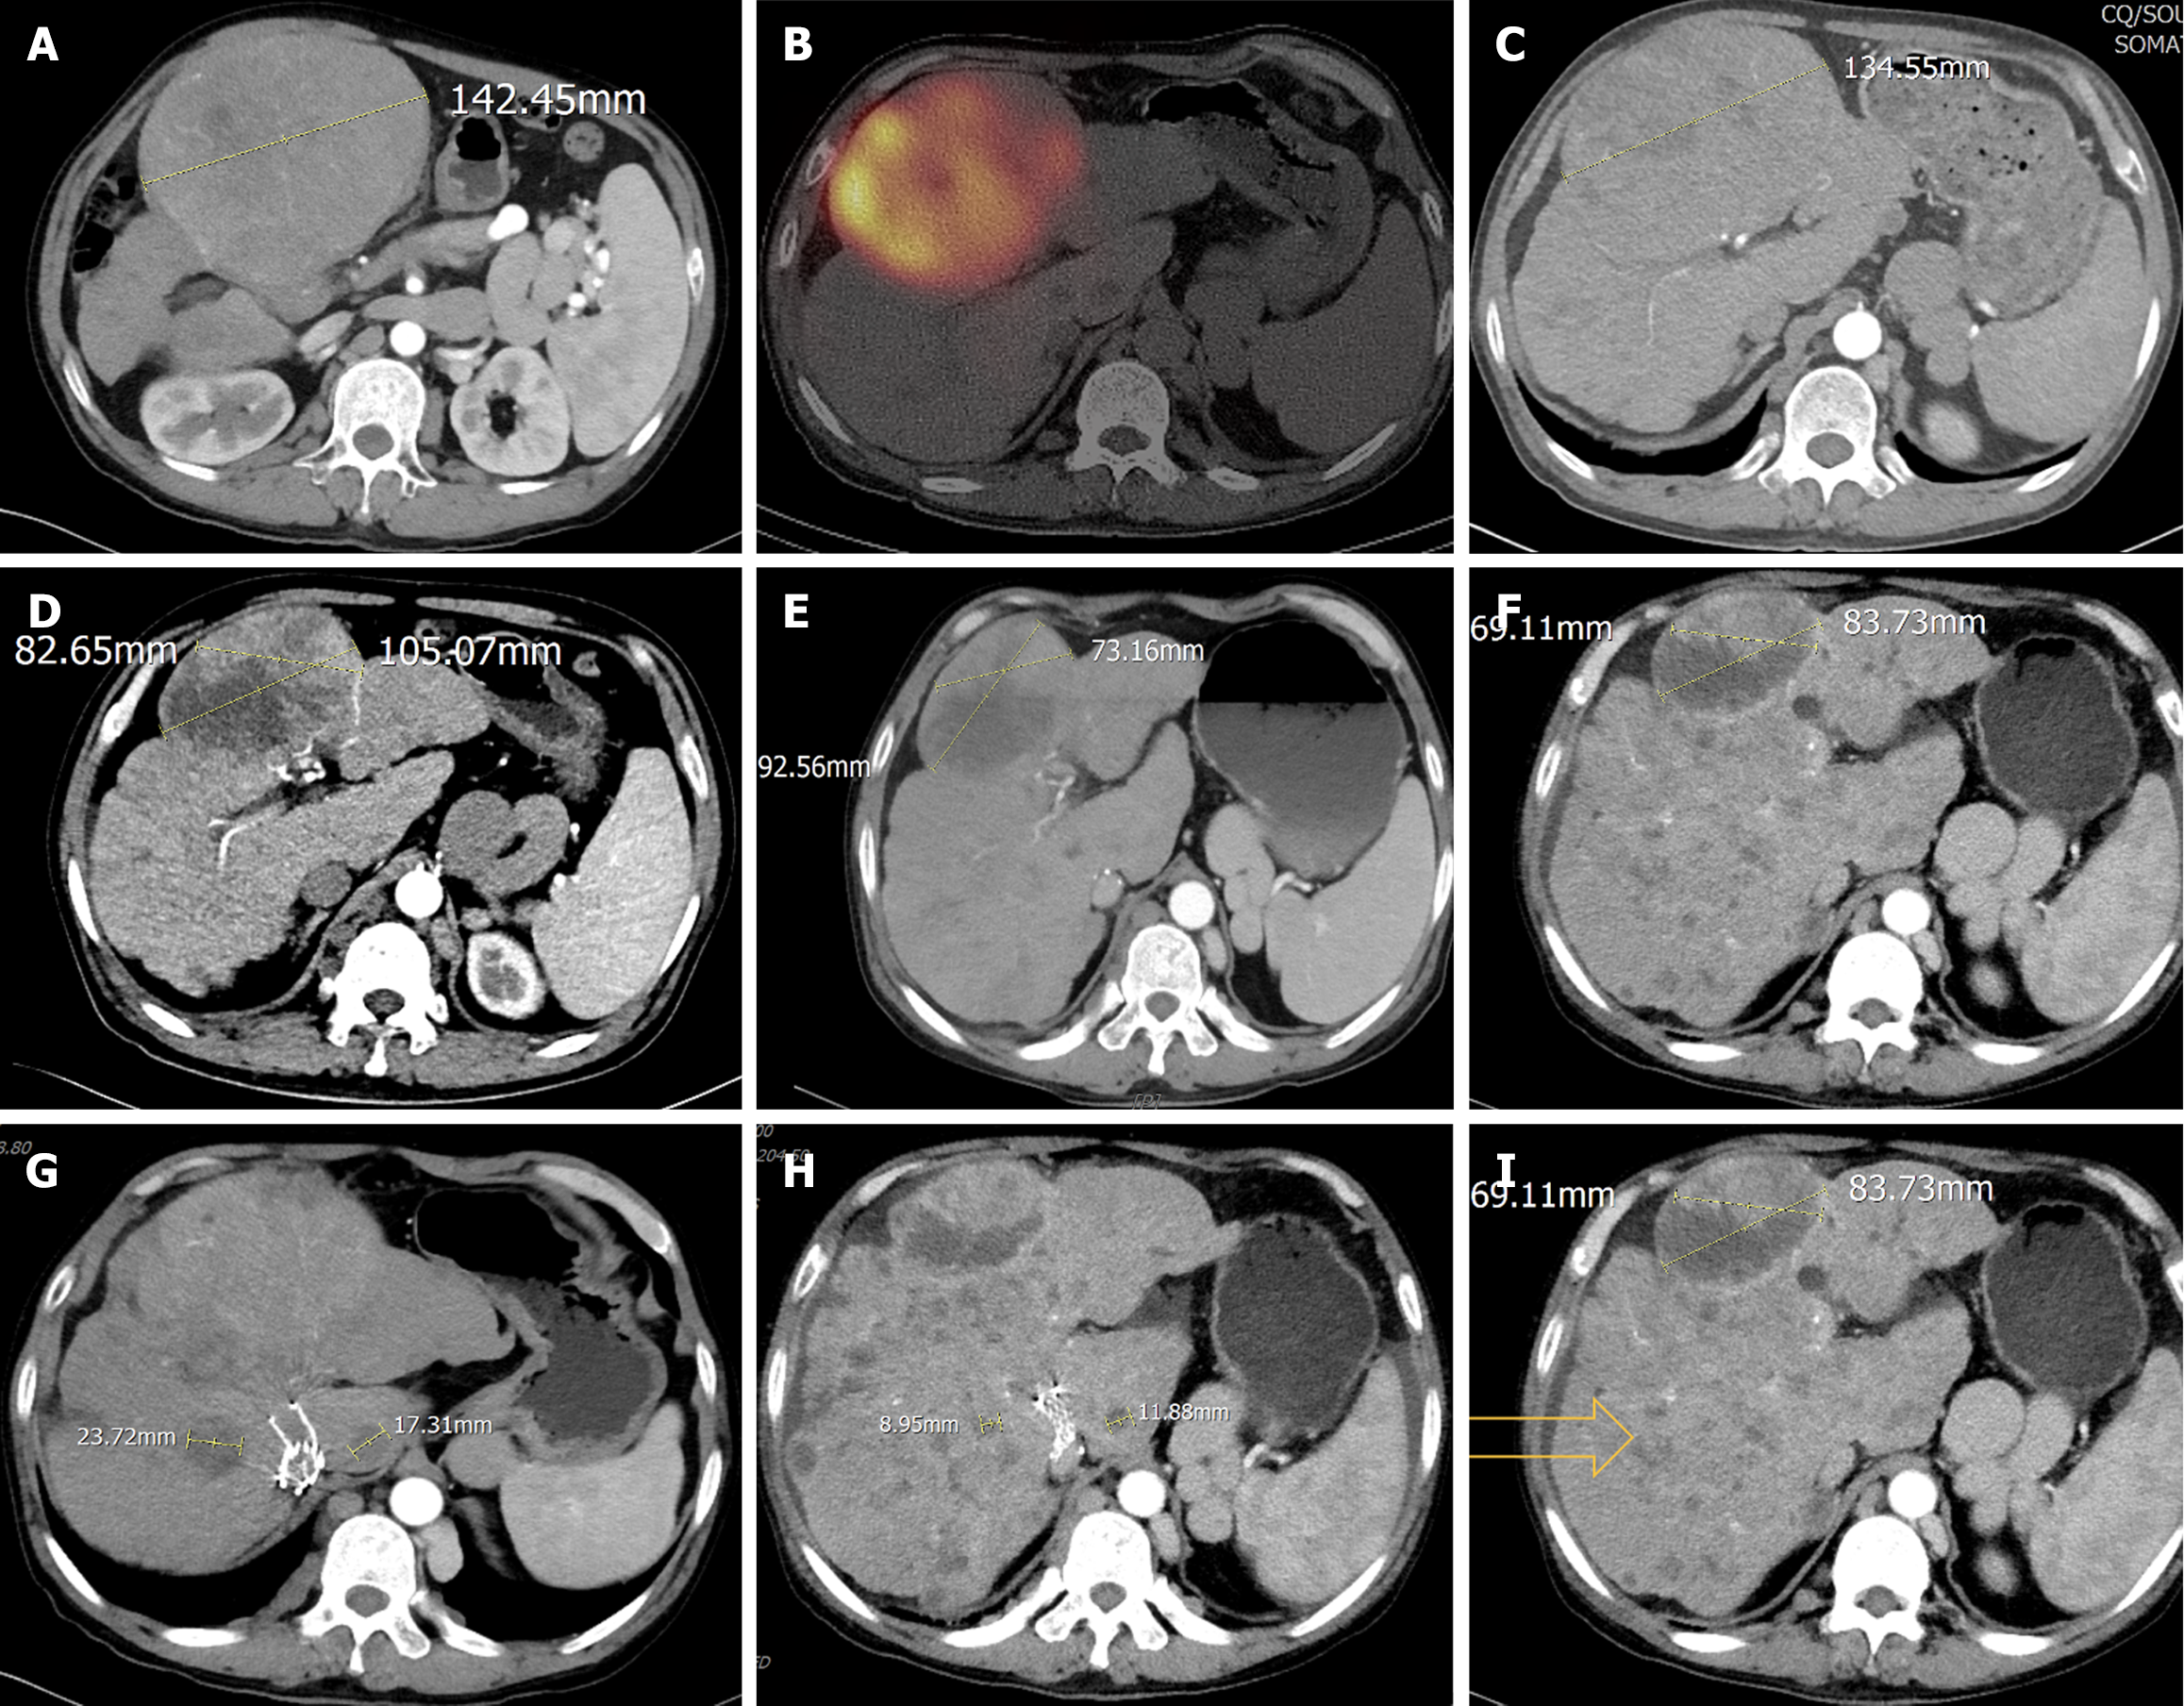

The current imaging assessment with enhanced computed tomography (CT) revealed ascites and exophytic massive HCC lesions located at the junction of the left and right liver lobes and multiple intrahepatic metastases (Figure 1), with a maximum tumor diameter [Barcelona Clinic Liver Cancer (BCLC) B] of 142.45 mm (Figure 1A).

The patient initially presented to our hospital on March 8, 2023. Upon admission, hepatoprotective therapy (glutathione and S-adenosyl-L-methionine-1,4-butane-disulfonate) and nutritional support were continued. On March 22, 2023, a Tc99m-MAA perfusion test was performed to evaluate the hepatic vascular architecture. Following a multidisciplinary discussion, lenvatinib was temporarily discontinued due to its potential impact on hepatic function and tumor perfusion. Hepatic arterial infusion chemotherapy was then initiated as an alternative therapeutic strategy. On May 13, 2023, Tc99m-MAA perfusion test was conducted again, the middle hepatic artery was mapped, confirming the absence of extrahepatic uptake, revealing a hepatic-pulmonary shunt fraction of 9.5%, which met the criteria for 90Y radioembolization. Subsequently, on May 25, 2023, the patient underwent 90Y radioembolization targeting the largest intrahepatic lesion (Figure 1B). For 90Y radioembolization with resin microspheres (SIR-Spheres®, Sirtex Medical), the prescribed activity was 3.4 GBq, with estimated tumor and lung absorbed doses of 140 Gy and 15.4 Gy, respectively. Single-photon emission CT/CT examination after 90Y injection revealed good deposition in the target tumor. This minimally invasive procedure delivers high doses of radiation directly to the tumor while sparing surrounding healthy tissue.

Post-treatment, the patients’ liver function improved to Child-Pugh class A, reflecting enhanced hepatic functional reserve. On May 14, 2023, a contrast-enhanced CT scan demonstrated a significant reduction in the maximum diameter of the tumor to 134.55 mm (Figure 1C), along with decreased tumor enhancement, indicating effective treatment response, PIVKA-II was 8697 mAU/mL, and AFP was 21.46 ng/mL. Given the improved clinical status, lenvatinib targeted therapy was reinitiated to further control disease progression. Hepatoprotective and nutritional support therapies were continued to maintain liver function and overall patient well-being.

One month after the procedure, the patient’s PIVKA-II level decreased to 1288 mAU/mL, and AFP level was 6.78 ng/mL (Figure 2). Liver function remained classified as Child-Pugh class A. The patient continued lenvatinib targeted therapy at a dose of 8 mg/day, along with hepatoprotective measures and nutritional support to promote liver function recovery. In the fourth month post-treatment (September 14, 2023), follow-up contrast-enhanced CT demonstrated extensive necrosis of the target lesion, with non-target intrahepatic lesions showing neither progression nor regression (Figure 1D). According to the modified Response Evaluation Criteria in Solid Tumors, the response was classified as partial response. At this time, PIVKA-II was 433 mAU/mL, AFP was 14.8 ng/mL (Figure 2), and liver function remained Child-Pugh class A. The patient was advised to consider liver transplantation but declined the suggestion.

By the sixth month post-treatment (November 2023), the patient developed scleral icterus. Contrast-enhanced CT revealed continued regression of the target lesion but little enlargement of non-target intrahepatic lesions (Figure 1E). PIVKA-II increased to 1153 mAU/mL, AFP was 22.85 ng/mL, and liver function deteriorated to Child-Pugh class B, with total bilirubin elevated to 62.2 μg/mL. Consequently, lenvatinib targeted therapy was discontinued, and the patient applicated with artificial extracorporeal liver support and continued with hepatoprotective measures, nutritional support. In the tenth month post-treatment (March 2024), follow-up CT showed continued shrinkage of the target lesion in the left medial lobe and the diameter of measurable non-target lesions reductions, but revealed multiple new small nodules in the remaining liver (Figure 1F and I). Additionally, pleural and peritoneal effusions were detected. At this time, PIVKA-II was 18431 mAU/mL, AFP was 26.61 ng/mL, and liver function further deteriorated to Child-Pugh class C, Eastern Cooperative Oncology Group performance status score was 1. The patient requested palliative care and passed away on August 18, 2024.